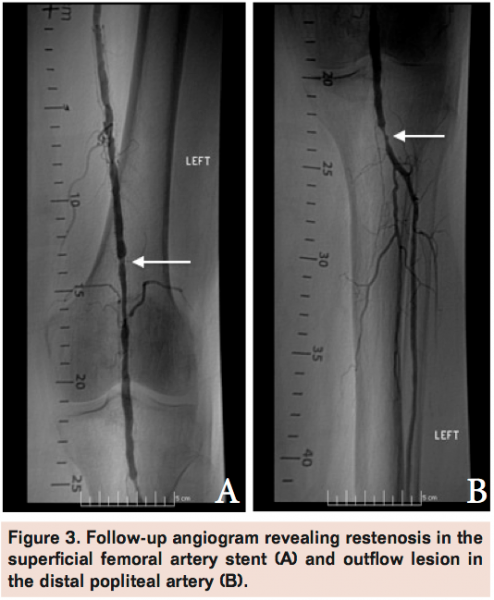

Angiogram of the left common femoral artery with runoff revealed distal left superficial femoral artery occlusion (Figure 1A) with reconstitution of the distal popliteal artery and 2-vessel runoff into the left foot via the anterior tibial and peroneal arteries (Figure 1B). Revascularization of the occlusion was performed using balloon angioplasty and stent placement (Figure 2A) with good angiographic result and runoff (Figure 2B). She had complete resolution of her claudication symptoms, but returned 1 year later with ulceration of the medial aspect of her left foot above the medial malleolus. Repeat angiogram revealed restenosis of the stent (Figure 3A) and re-occlusive disease of the distal popliteal artery stent extending into the anterior tibial artery (Figure 3B) requiring atherectomy and balloon angioplasty for successful revascularization (Figure 4). However, her ulceration progressed despite revascularization, prompting further evaluation of the etiology of her ulcer (Figure 5). A venous Doppler study of the left lower extremity revealed severe reflux of the left greater saphenous vein (Figure 6) with flow above baseline in the proximal, mid, and distal portions of up to 1.7 seconds. An incompetent perforating vein was also noted in the left calf 23 cm from the ankle and measured at 0.33 cm in diameter (Figure 7). She subsequently underwent radiofrequency ablation of the left greater saphenous vein followed by the left calf perforator with complete occlusion by ultrasound (Figure 8).